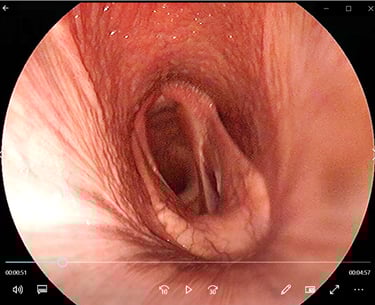

Longonderzoek (endoscopie, echografie, tracheal wash, radiografie)

Mobiele endoscopie/echografie - Consult aan huis

Heeft uw paard last van een aanhoudende of terugkerende hoest? Dan is het aangewezen om een endoscopie (cameraonderzoek) van de luchtwegen te laten uitvoeren. Hoesten wordt namelijk niet altijd veroorzaakt door astma. Tijdens het onderzoek kunnen we ook stalen nemen voor microscopisch en bacteriologisch onderzoek. Op basis van deze resultaten stellen we een behandelplan op maat van uw paard op.

In sommige gevallen is aanvullend een echografie van de longen aangewezen. Dit wordt steeds per situatie beoordeeld en met u besproken.

Longonderzoeken worden uitgevoerd op locatie in heel België, Nederland, Frankrijk, Duitsland en Luxemburg.